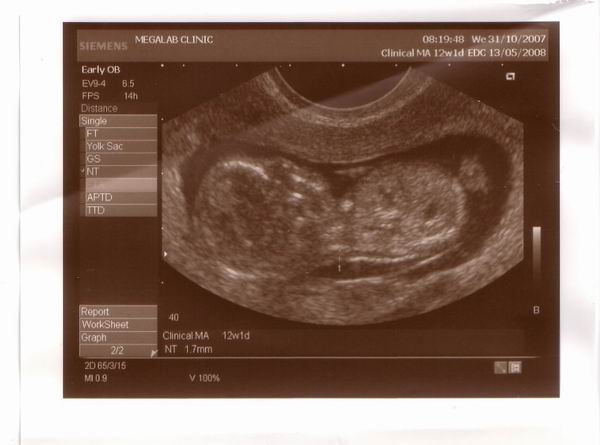

Megjöttünk, minden rendben volt, az értékei jók, bár a neten sehol sem találom, hogy mik a jó értékek, csak a genetikus nőci mondta. Egyedül a tarkóredőt tudom, hogy 1,8 ami jó, mert 3 mm alatt kell lennie. CRL az 59,4 mm, az szerint 12+2 hetes.

köszönöm, és a táblázatot is, éppen néztem, hogy amikor először voltunk uh-n, akkor 6+3 hetes volt és 8 mm, tehát akkor is már 6+4-nek felelt meg, azután a 9+0 uh-n szintén 9+1-et mondtak, bár akkor nem mondták nekem a CRL-t, most meg szintén 12+1 helyett 12+2-nek felel meg. Szerintem ha három különböző időben nézték, meg mindig egy nappal volt nagyobb, akkor ezek szerint biztosra vehetem, hogy a babus a 14. napon fogant, mert a kalkulátorok szerint a 15.-en. Ami persze azt is jelenti, hogy a szülés várható ideje, ha pont 40 hétre születik, hogy május 12, ami apa szülinapja. Hát ez nem semmi. Ha akartuk volna sem tudtuk volna igy összehozni. :D

Egy kissé megkésve, de ime a kép:

Bár elég rossz minőségű! :(